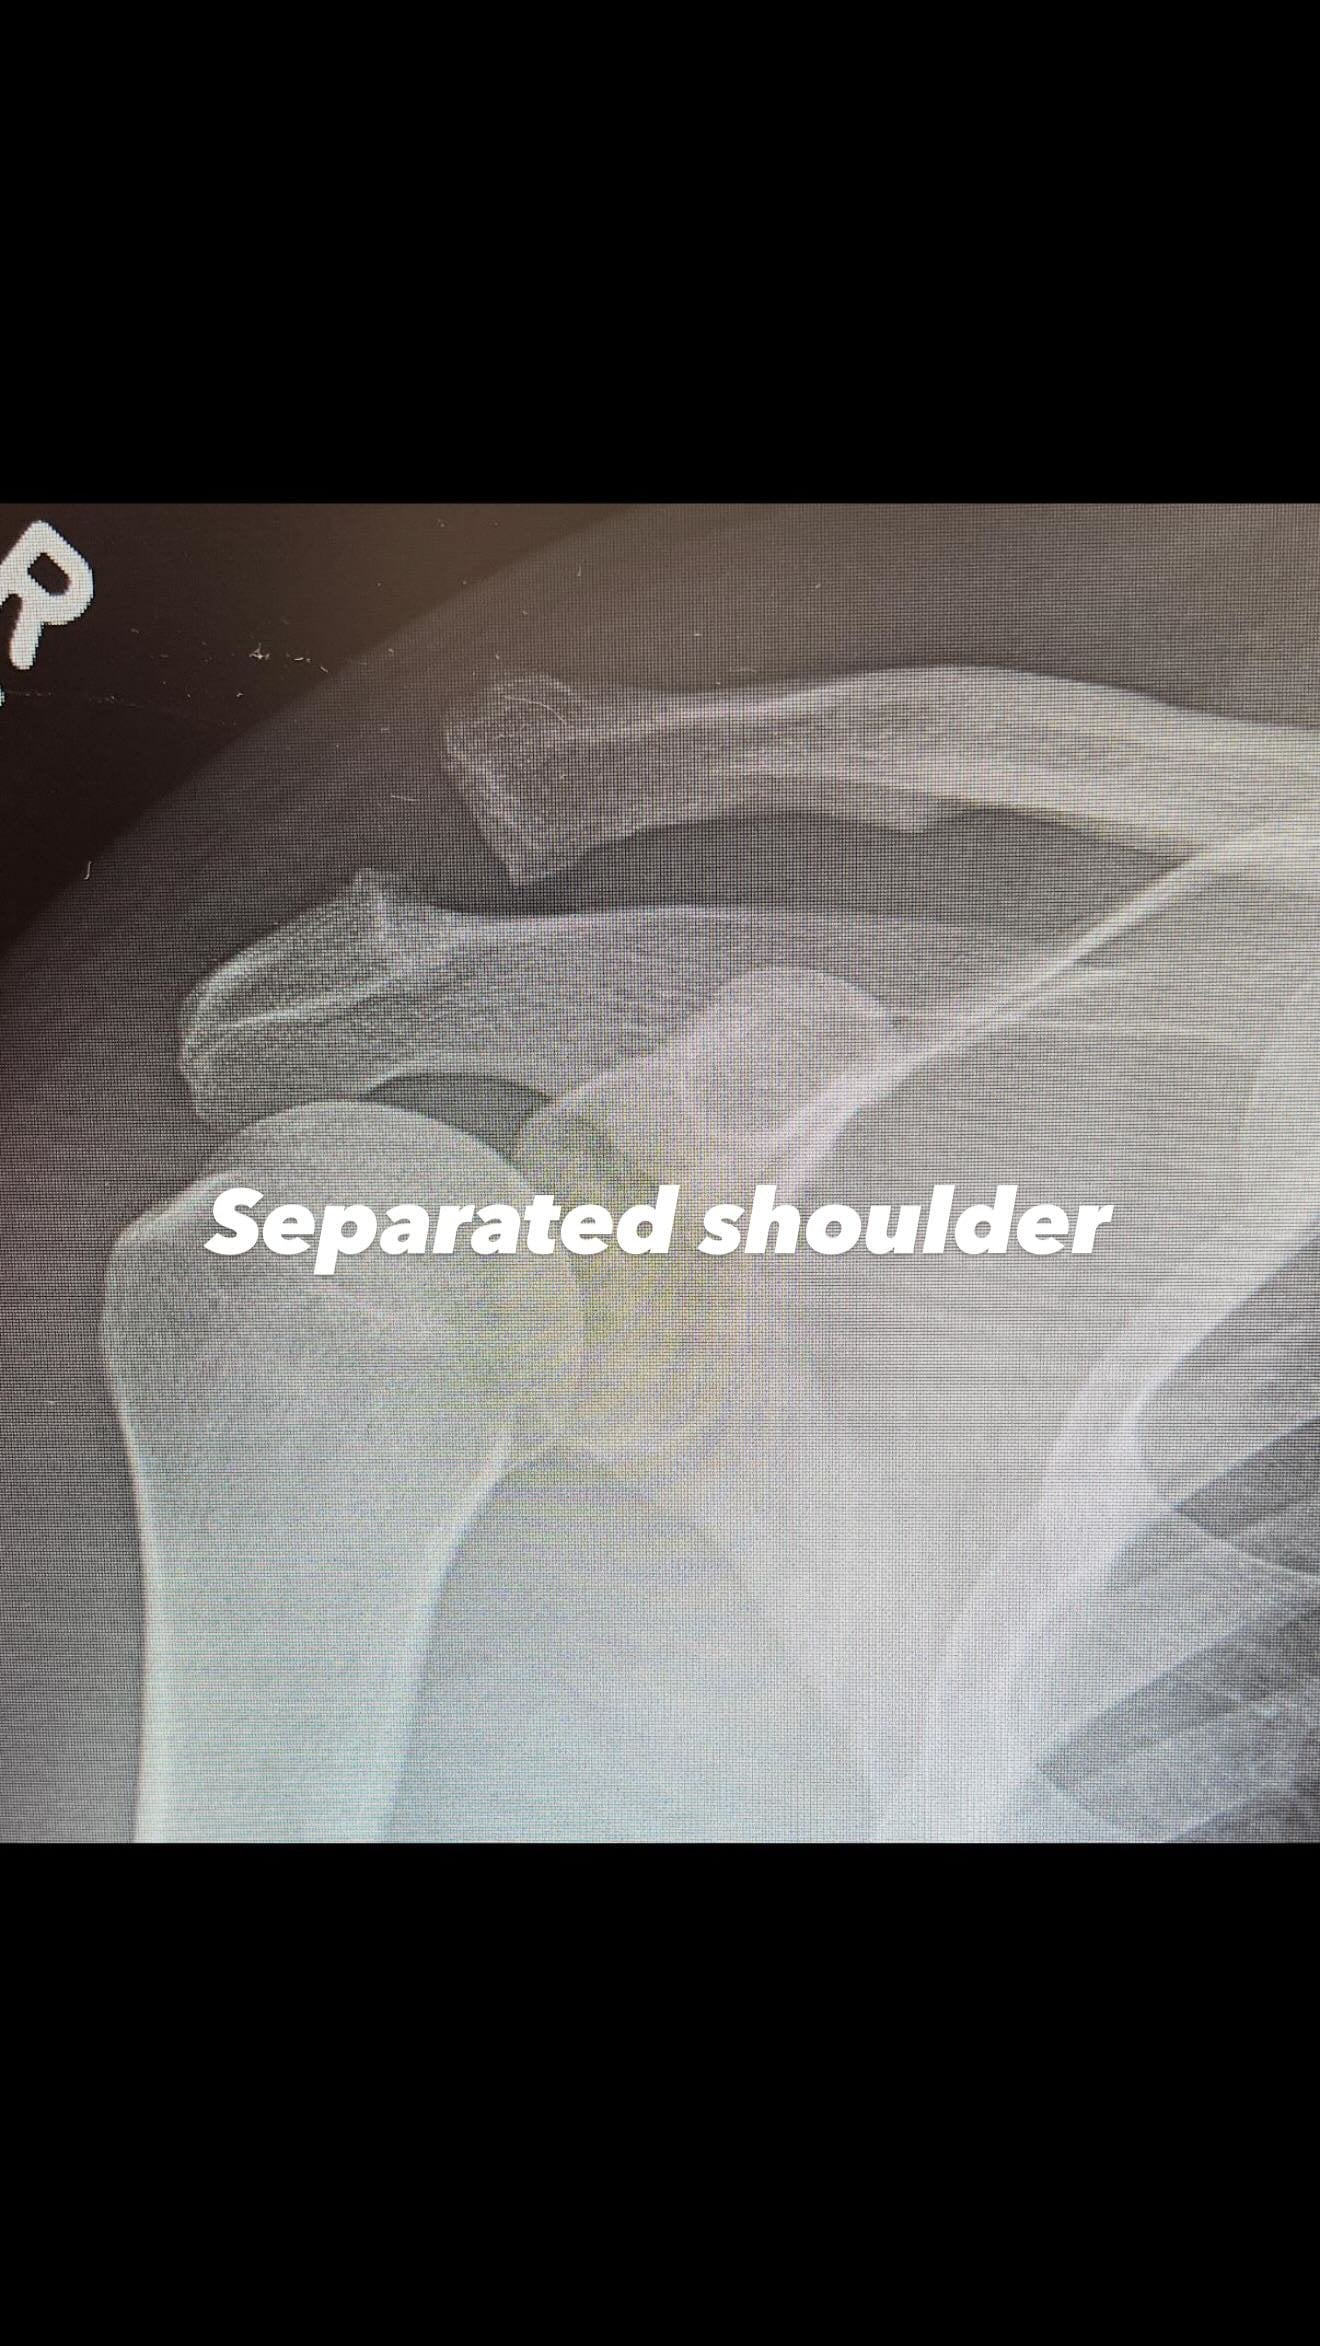

Як виявилося, Ченнінг Татум переніс операцію. Хірургічне втручання йому знадобилося на плечі, оскільки він дістав серйозну травму. В актора вивих акроміально-ключичного суглоба. Щоб вправити плече на місце, довелося робити операцію.

Плече Ченнінга Татума до операції / © instagram.com/channingtatum

Ченнінг Татум уже показав рентгенівський знімок до та після хірургічного втручання. Актор не став розкривати, як саме дістав травму, лише запевнив, що впорається з усіма негараздами, хоча це й буде нелегко.